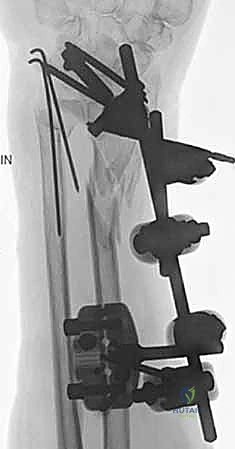

ثانياً: العلاج الجراحي (Surgical Intervention)

متى يقرر الدكتور هطيف ضرورة التدخل الجراحي؟

1. عدم الاستقرار (Instability): إذا كان المفصل الزندي الكعبري البعيد (DRUJ) غير مستقر بعد تثبيت كسر الكعبرة.

2. الانزياح (Displacement): إذا كان الكسر في قاعدة الناتئ الإبري منزاحًا بأكثر من 2 ملم.

3. الكسور المفصلية: أي كسر يخل بتطابق السطح المفصلي لرأس الزند.

4. الكسور المفتتة: في الجزء الكردوسي التي تؤدي إلى قصر عظم الزند.

5. الكسور المفتوحة (Open Fractures): حيث يبرز العظم من الجلد، وتتطلب جراحة طارئة لتنظيف الجرح وتثبيت الكسر لمنع العدوى.

خطوات التدخل الجراحي الدقيق مع الأستاذ الدكتور محمد هطيف

تُعد جراحات المعصم والزند من الجراحات الدقيقة التي تتطلب مهارة عالية، وهو المجال الذي يتفوق فيه الأستاذ الدكتور محمد هطيف بفضل استخدامه لتقنيات الجراحة المجهرية (Microsurgery) والأدوات الجراحية ذات التقنية العالية.

1. التخطيط ما قبل الجراحة (Pre-operative Planning)

يقوم الدكتور هطيف بدراسة الأشعة المقطعية ثلاثية الأبعاد بدقة، ويختار نوع وحجم الصفائح المعدنية (Plates) والمسامير (Screws) المناسبة لكل مريض بناءً على حجم العظم ونوع الكسر.